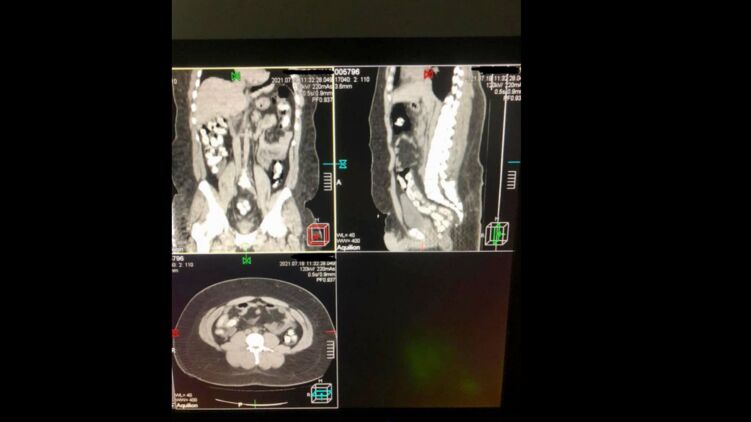

Имея предварительную оперативную информацию, таможенники применили в отношении 29-летнего мужчины личный досмотр с привлечением медицинского работника. Процедура проходила в медицинском учреждении с применением компьютерной томографии брюшной полости мужчины.

Наркокурьер оказался классическим "глотателем", который перевозит наркотики в герметичных капсулах, используя для этого собственный желудок.

Изъятие 90 капсул овальной формы, которые находились в его кишечнике, происходило медикаментозным путем и длилось почти три часа подряд. Вес брутто обнаруженного – 965 г. По результатам экспресс-анализа, обнаруженное является кокаином.